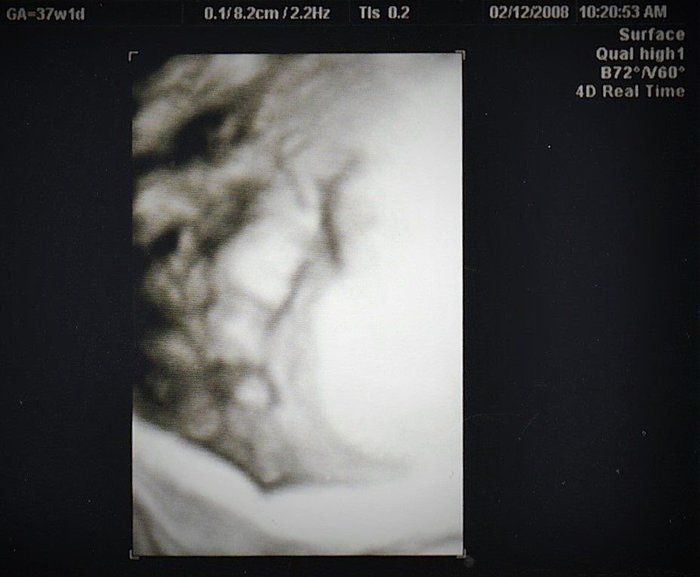

Tomomiさんの妊娠37週目のエコー写真 最後のエコー写真 明日会えるね!!

手術前日のベビちゃん。お手てをギュッと握って、穏やかなお顔でした。

「いつから首にへその緒が巻きついていたのかな?身動き取れなくて居心地悪かったのかな?」

静かな病室のベッドでおなかを撫でながら話かけたり、一緒に過ごした日々を思い返していました。

「手術は怖いけれど、ママ頑張るね。一緒に頑張ろうね」。